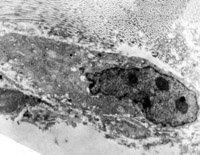

5-2-2 傷后第1天,毛細(xì)血管內(nèi)皮細(xì)胞核固縮,管腔內(nèi)血液凝集和瘀滯  TEM×6000